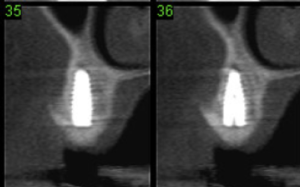

Tomografia pré-operatória.

Tomografia pós-operatória de quatro meses. Notar que aparenta regeneração óssea na região da tábua vestibular e terço cervical sob a membrana.